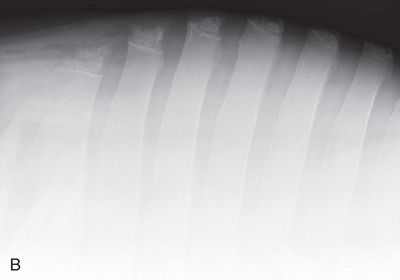

| Thoracic spine | Lateral (Fig. 24.59) | Side of the patient on area of interest. | Opposite side. | Area of interest perpendicular to the image receptor. | Often completed for the dorsal spinous processes (withers). |